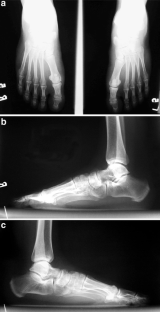

A 35-year-old woman presented with bilateral leg pain on walking that had been present since childhood. Clinical examination showed bilateral absence of the tibialis anterior tendons and the left extensor hallucis longus tendon. Magnetic resonance imaging revealed that signal intensities in the location of the tibialis anterior muscles bilaterally and the left extensor hallucis longus muscle were uniformly high on T1-weighted images, consistent with fat tissue and aplastic muscles: findings not previously reported.

Fig. 1